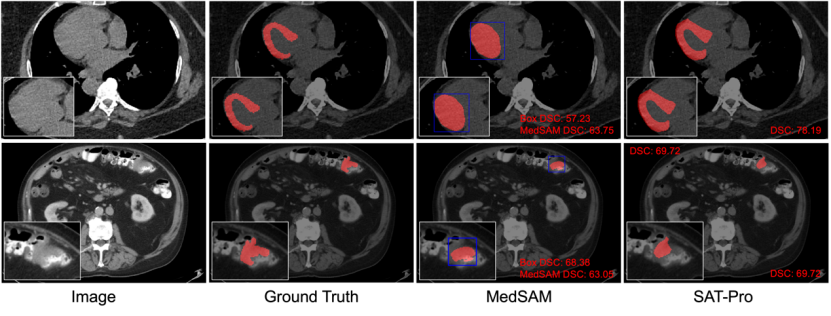

定性比较:图6从域内测试的结果中挑选了两个典型例子进行可视化展示,进一步对比SAT和MedSAM。如图6上所示,在对心肌的分割中,Box提示很难区分心肌和被心肌包裹的心室,因此MedSAM也错误将两者一起分割了出来,这表明Box提示在类似的复杂空间关系中很容易有歧义,导致分割不精准。

相比之下,基于文本提示(直接输入解剖结构的名字)的SAT可以精准地区分心肌和心室。此外,在图6下展示的肠道肿瘤分割中可以看到,Oracle Box对于病灶目标来说已经是很好的预测结果,而MedSAM的分割结果可能不会比所得到的Box提示更好。

图 6:SAT-Pro与MedSAM(Tight)的定性比较。其中MedSAM使用Oracle Box作为提示,Box用蓝色标识。第一行展示了一个心肌分割的例子;第二行展示了一个肠道肿瘤分割的例子。